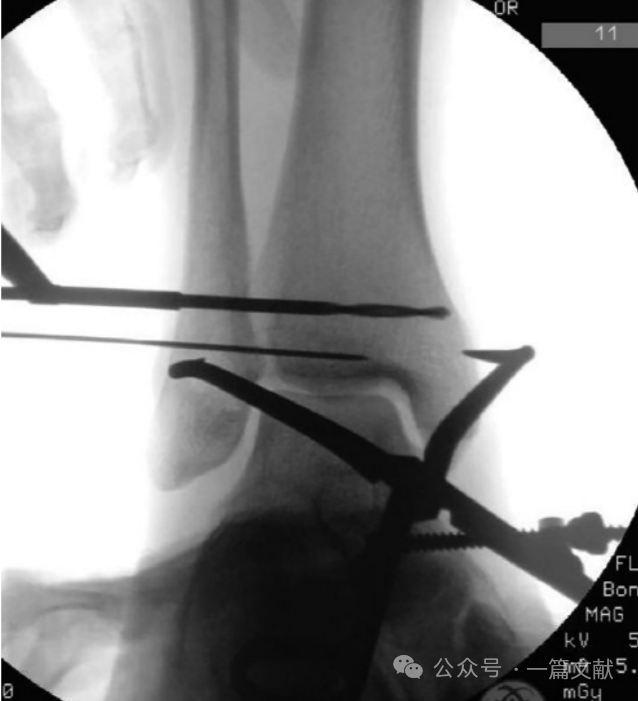

“下胫腓联合损伤的解剖复位并不容易实现”。考虑到部分患者的解剖学变异,可能硬币征不一定完全准确。所以消毒铺单前对健侧踝关节的标准侧位与踝穴位透视非常重要。这样才能获得可靠的参考标准。必要时可做有限的前外侧切口来复位与固定,于趾伸肌腱和第三腓骨肌进入。术中复位以后打入1枚克氏针临时固定,并透视标准侧位,与健侧对比,来判断复位情况。

这张对比图像的重点是观察腓骨与胫骨的前后方向相对位置,来判断腓骨是否有前后移位。以及腓骨的投影大小,来判断腓骨是否有旋转。当克氏针穿透腓骨并进入胫骨切迹时,复位钳轻轻夹持复位,此时要避免过度复位。